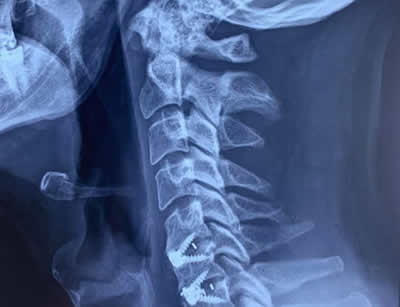

GALLERY

Images gallery